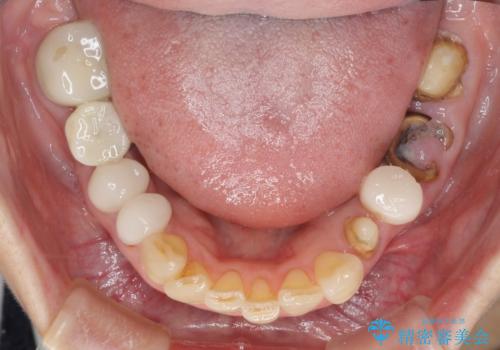

- 虫歯や歯の欠損を放置していることを気にして来院された患者様です。

下顎には抜歯が必要な歯があったため、抜歯後に治癒を待ち、上顎とともにオールセラミックブリッジにて補綴治療を行うこととしました。